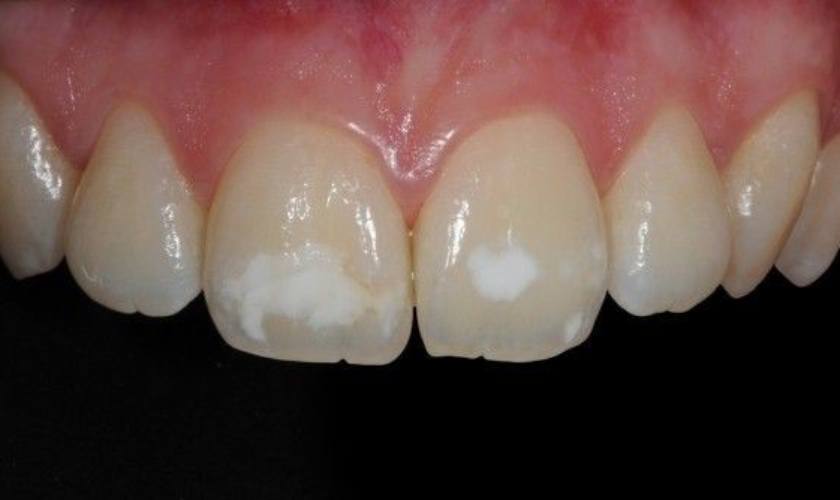

Răng trẻ em có đốm trắng là bị gì? Đây là hiện tượng bất thường ở răng thường gặp ở nhiều trẻ. Những đốm trắng có màu đục trên răng khiến răng trẻ bị mất thẩm mỹ.

Trong nha khoa, tình trạng răng xuất hiện những vệt hay đốm trắng đục được gọi là hiện tượng răng nhiễm Fluor.

Tuy nhiên, bất kỳ chất dinh dưỡng nào, nếu sử dụng quá nhiều dẫn đến dư thừa thì cũng gây ra tác dụng ngược. Trẻ bị dư thừa Fluor sẽ khiến răng phát triển bất thường, hình thành những đốm trắng màu đục hoặc vàng ở men răng.

Phần răng tại vị trí đốm trắng rất giòn và dễ vỡ, dễ bị ăn mòn và tấn công bởi vi khuẩn. Do đó, răng rất dễ bị sâu, nứt, mẻ, vỡ ở những vị trí này.

Răng tại vị trí đốm trắng khá giòn và dễ bị sâu, mẻ, vỡ

Ảnh hưởng đầu tiên của răng bị nhiễm Fluor là gây mất thẩm mỹ cho hàm răng của trẻ, răng sẽ không đều màu mà xuất hiện những đốm trắng loang lổ khiến trẻ mất tự tin khi cười hay giao tiếp.

Thứ hai, răng có đốm trắng sẽ yếu hơn răng bình thường, vị trí đốm trắng rất dễ bị tác động và tổn thương như sâu, gãy, viỡ, nứt, mẻ răng. Vì vậy, răng nhiễm Fluor sẽ tăng nguy cơ bệnh lý răng miệng và chấn thương răng.